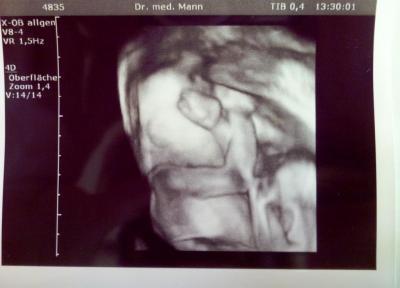

Hallo Mädels, ich war heute nochmal bei meinem FA ... letzten Mittwoch hat das Ultraschallgerät gestreikt und ich durfte heute nochmal kommen. Zuerst hat die Maus geschlafen und wollte sich nicht zeigen. Sie hat ihre Arme verschrenkt vors Gesicht gehalten - "Hey, nicht gucken. Ich möchte schlafen!" Nach längerem Warten und rütteln des Schallkopfes hat sie sich doch noch bewegt und ihr Gesicht gezeigt. Und ein erneuter Blick zwischen die Beine bestätigte nun zum dritten Mal das Outing - Mädchen, nun auch mit Beweisfoto! Viele Grüße, Claudia

Total schöne Bilder! Echt süß wie sie die Arme verschränkt hält! Herzlichen Glückwunsch dass es auch weiterhin und nun endgültig beim Mädchen bleibt!!!